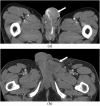

Angiosarcoma is a rare, aggressive subtype of soft-tissue sarcoma with a propensity for local recurrence and metastasis associated with a generally poor prognosis, unless diagnosed early. Given the vascular endothelial cell origin of angiosarcoma, tumours may develop in essentially any organ; however, there is a predilection for the skin where half of all tumours arise, increasing in prevalence with age. The most common risk factors are chronic lymphoedema and history of radiation. We review the most important radiological findings along the spectrum of angiosarcoma from head to toe throughout the body, including uncommon and rare locations. Key imaging features of angiosarcoma across multiple organ systems will be described, as well as the impact on management and prognosis.